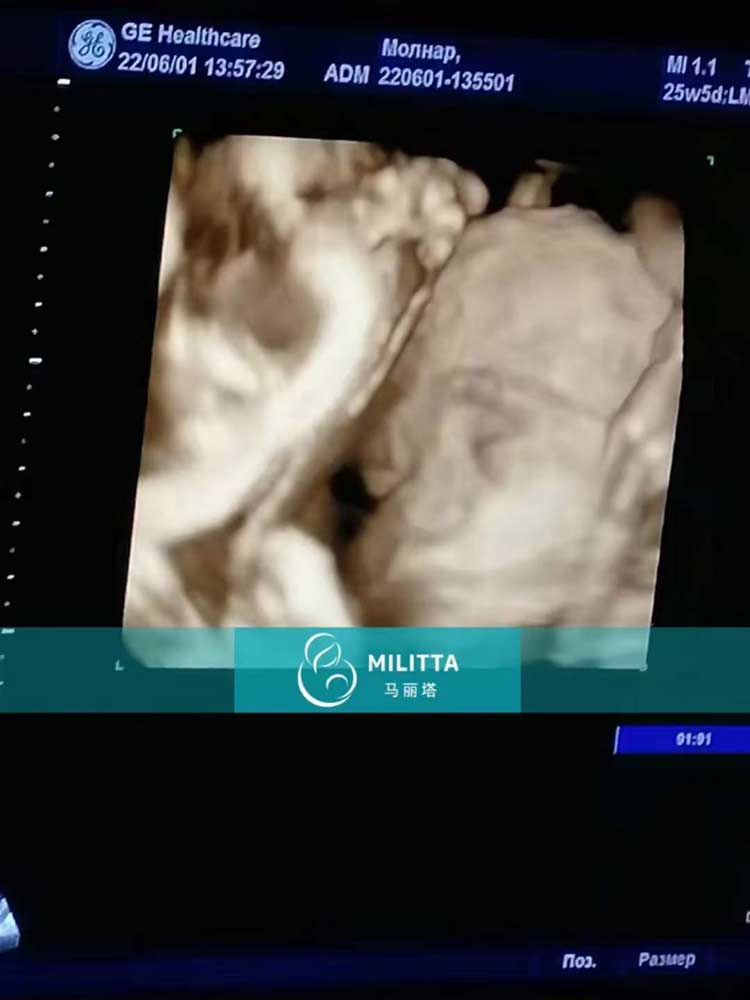

安排四位乌克兰试管妈妈去医院照了B超检查胎儿发育情况

安排四位乌克兰试管妈妈去医院照了B超检查胎儿发育情况,请父母们放心,胎宝宝们检查一切健康